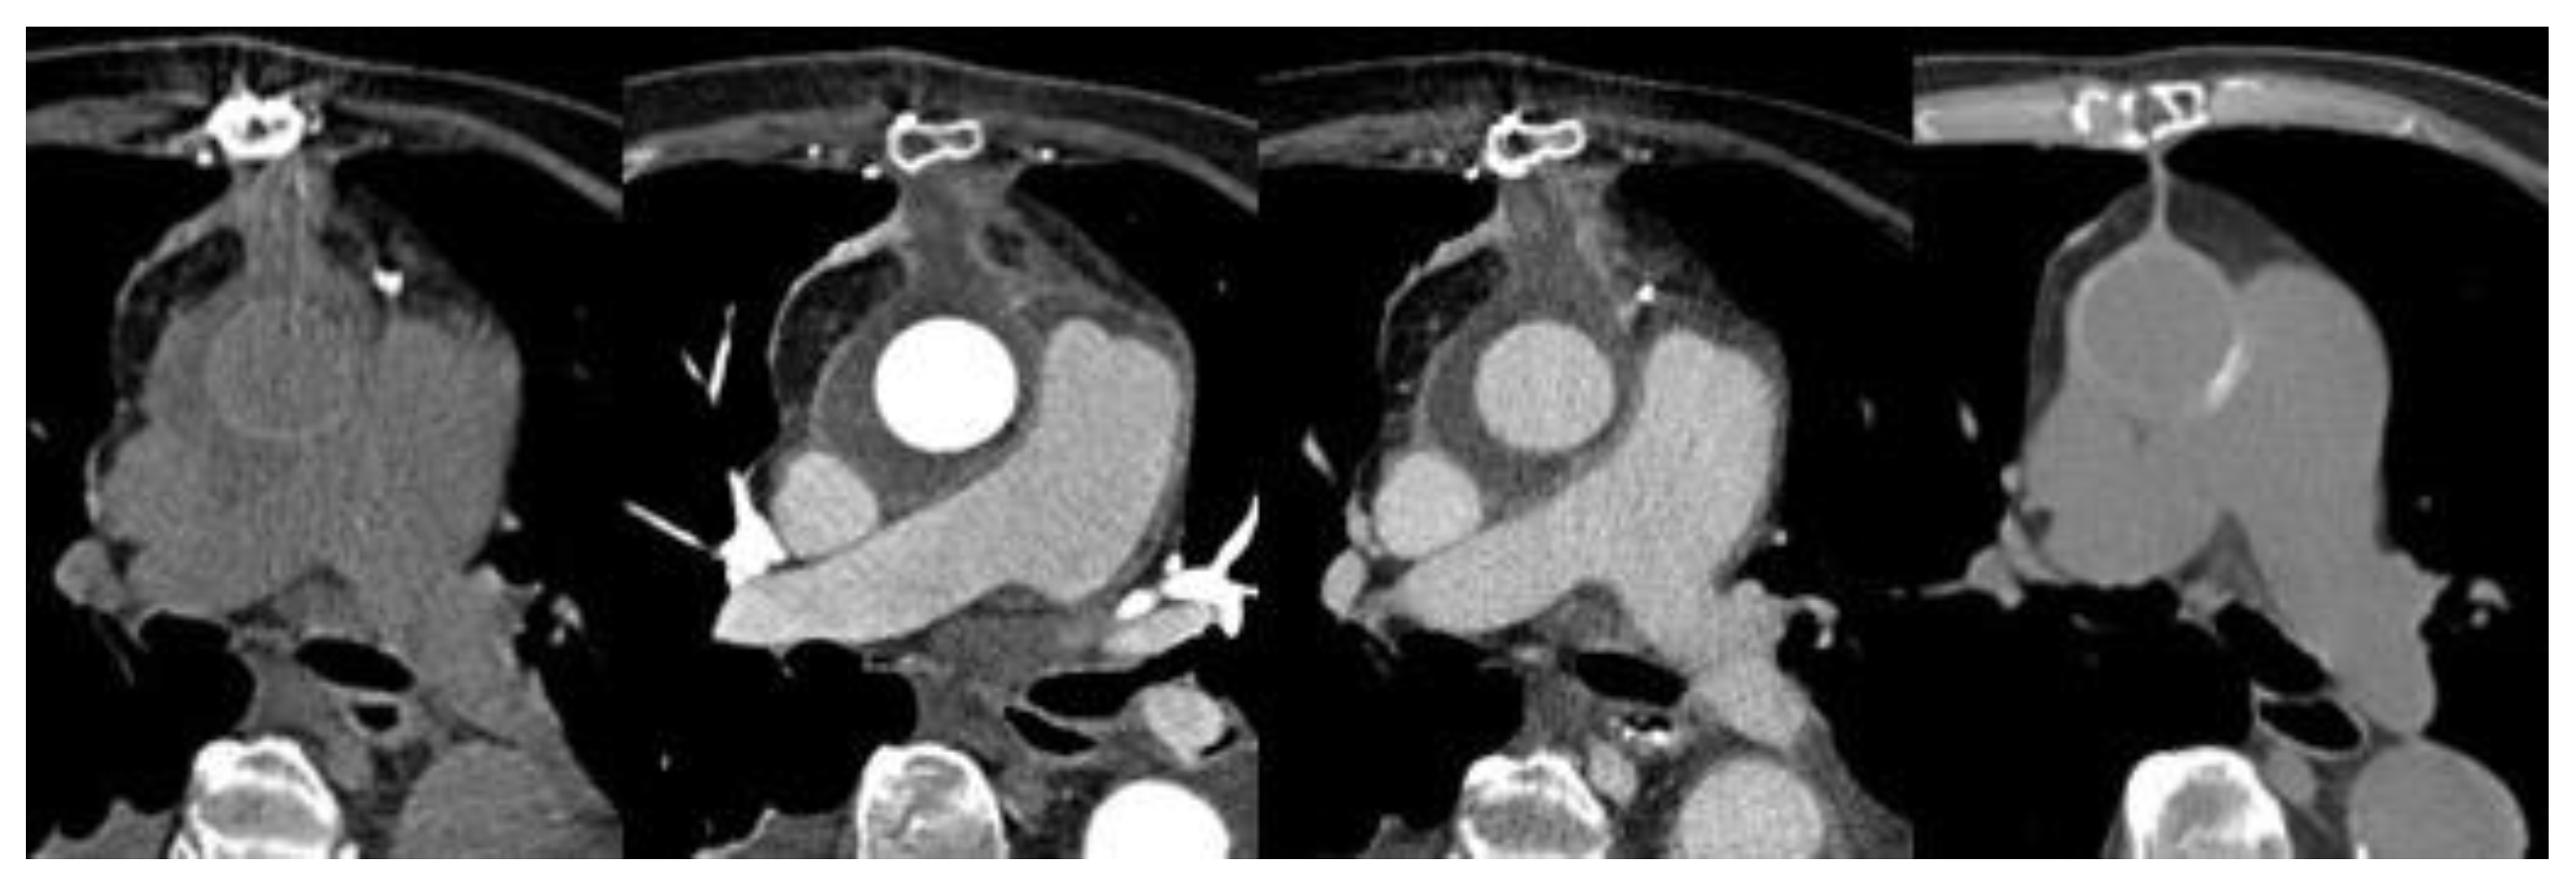

3.2. Computed Tomography (CT)—CT–Angiography (CTA)